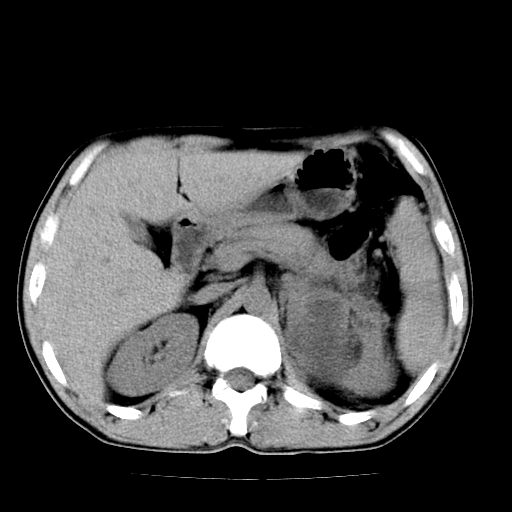

以下是引用天南地北在2007-4-30 13:36:00的发言:[br]支持慢性胰腺炎伴有假性囊肿

以下是引用andymaomao在2007-4-30 14:28:00的发言:[br]支持:1.慢性胰腺炎并假性囊肿形成可能;[br] 2.左肾形态稍增大,旋转不良。